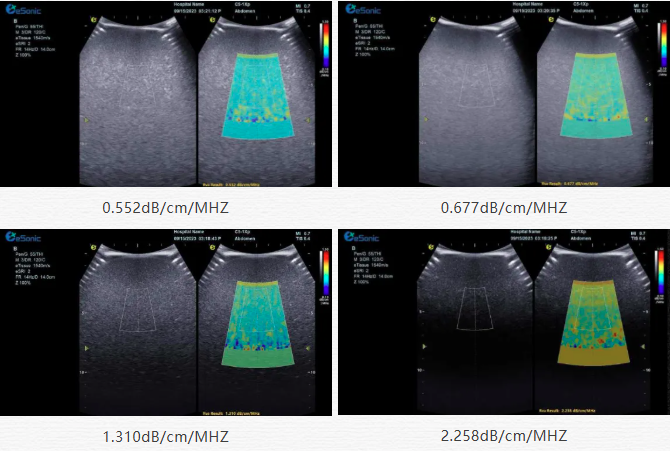

该技术基于声波在介质传播时的衰减,衰减由声吸收、反射、散射及波束扩散所致,声衰减系数(α,单位 dB/cm?MHz,与超声频率和传播距离成正比)可通过测定同频超声波在组织中的衰减程度,借回波信号分析预测声衰减系数或衰减率来评估组织特性。

目前市面常用瞬时弹性成像或仿体参照法,存在适用性、准确性差及无衰减图局限。百乐博平台则采用准确度更高的 ALA 幅度损失衰减法,超声波深度传播时回波幅度渐降,其对数与深度有良好线性关系,声衰减量与传播衰减系数成函数关系,调节取样框大小位置可实时得样框内组织衰减系数,用于定量评估病变程度。